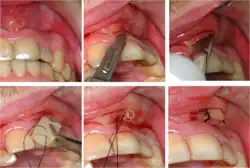

Root canal treatment (blue arrows) carried out on the lower right first molar with temporary restoration in place

Incision of an abscess above a front tooth and insertion of a surgical drain

Dental abscesses

A general principle concerning dental abscesses is ubi pus, ibi evacua ("where there is pus, drain it"), which applies to any case where there is a collection of pus in the tissues (such as a periodontal abscess, pericoronal abscess, or apical abscess). The pus within the abscess is under pressure, and the surrounding tissues are deformed and stretched to accommodate the swelling. This leads to a sensation of throbbing (often in time with the pulse) and constant pain. Pus may be evacuated via the tooth by drilling into the pulp chamber (an endodontic access cavity). Such a treatment is sometimes termed open drainage. Drainage can also be performed via the tooth socket, once the causative tooth is extracted. If neither of those measures succeeds, or they are impossible, incision and drainage may be required, in which a small incision is made in the soft tissues directly over the abscess at the most dependent point. A surgical instrument such as a pair of tweezers is gently inserted into the incision and opened, while the abscess is massaged to encourage the pus to drain out. Usually, the reduction in pain when the pus drains is immediate and marked as the built up pressure is relieved. If the pus drains into the mouth, there is usually a bad or offensive taste.